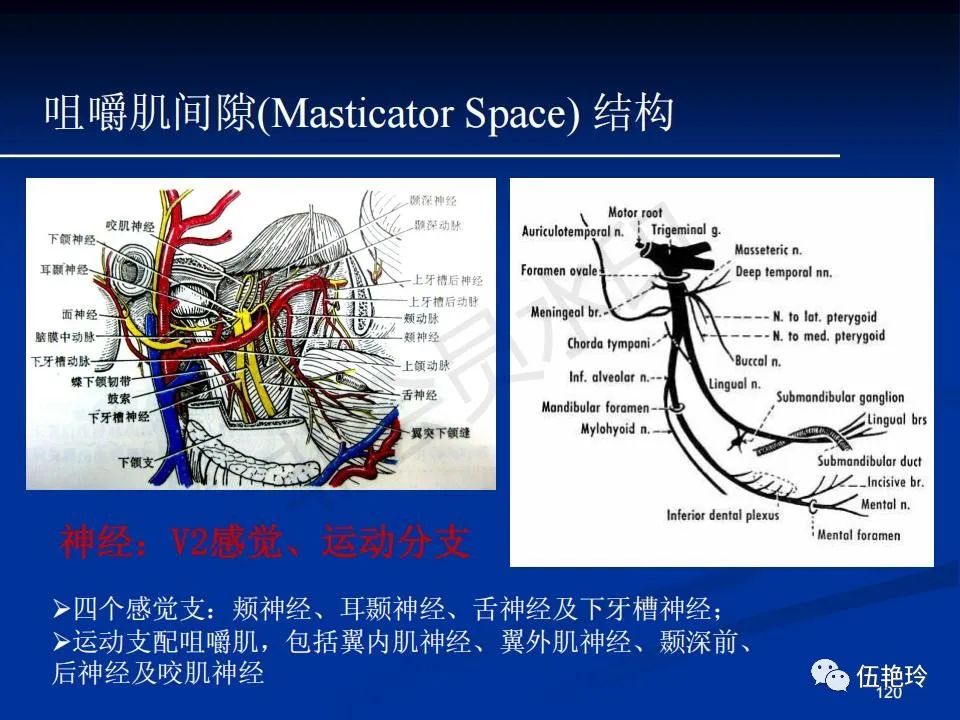

颞下窝与咀嚼肌间隙